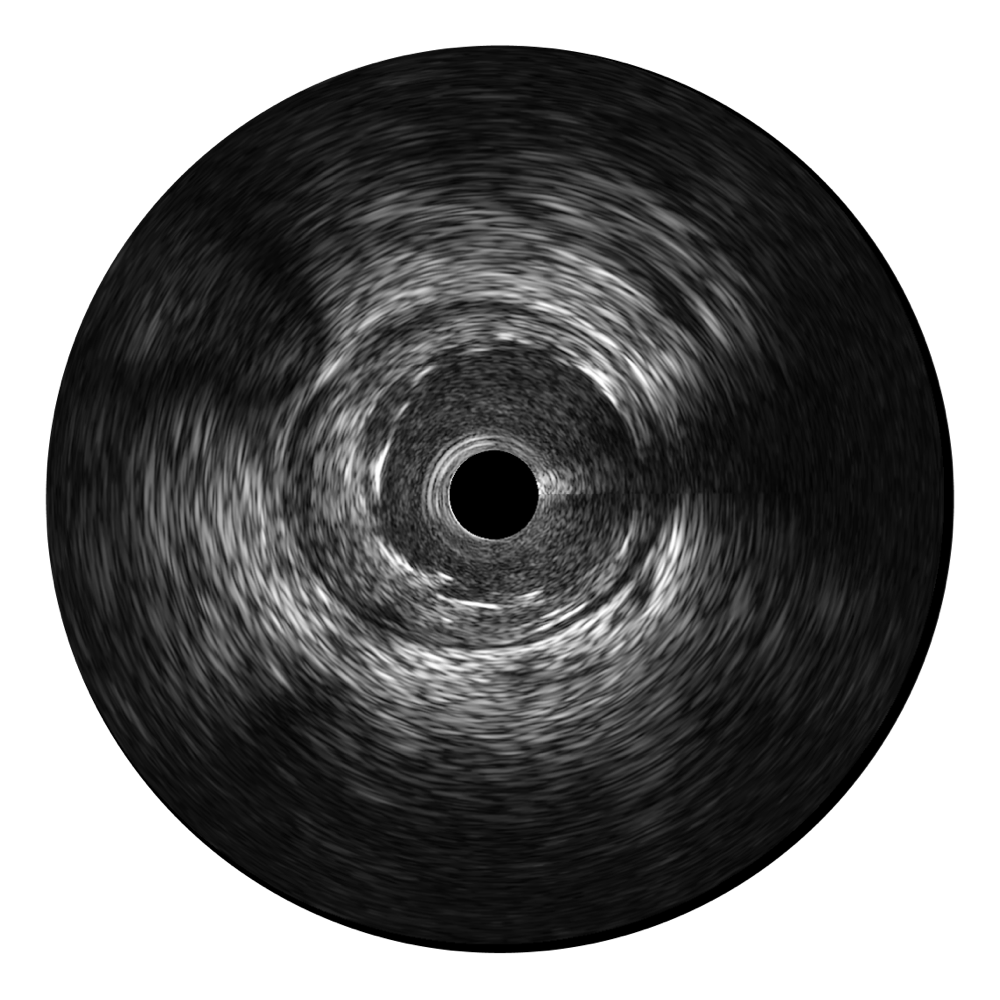

传统IVUS图像

对比传统IVUS导管成像,MILE米乐集团官网宽频IVUS图像的近场支架梁显影更细腻,远场中膜外血管仍清晰可辨,兼顾远中近,兼顾分辨力与穿透深度